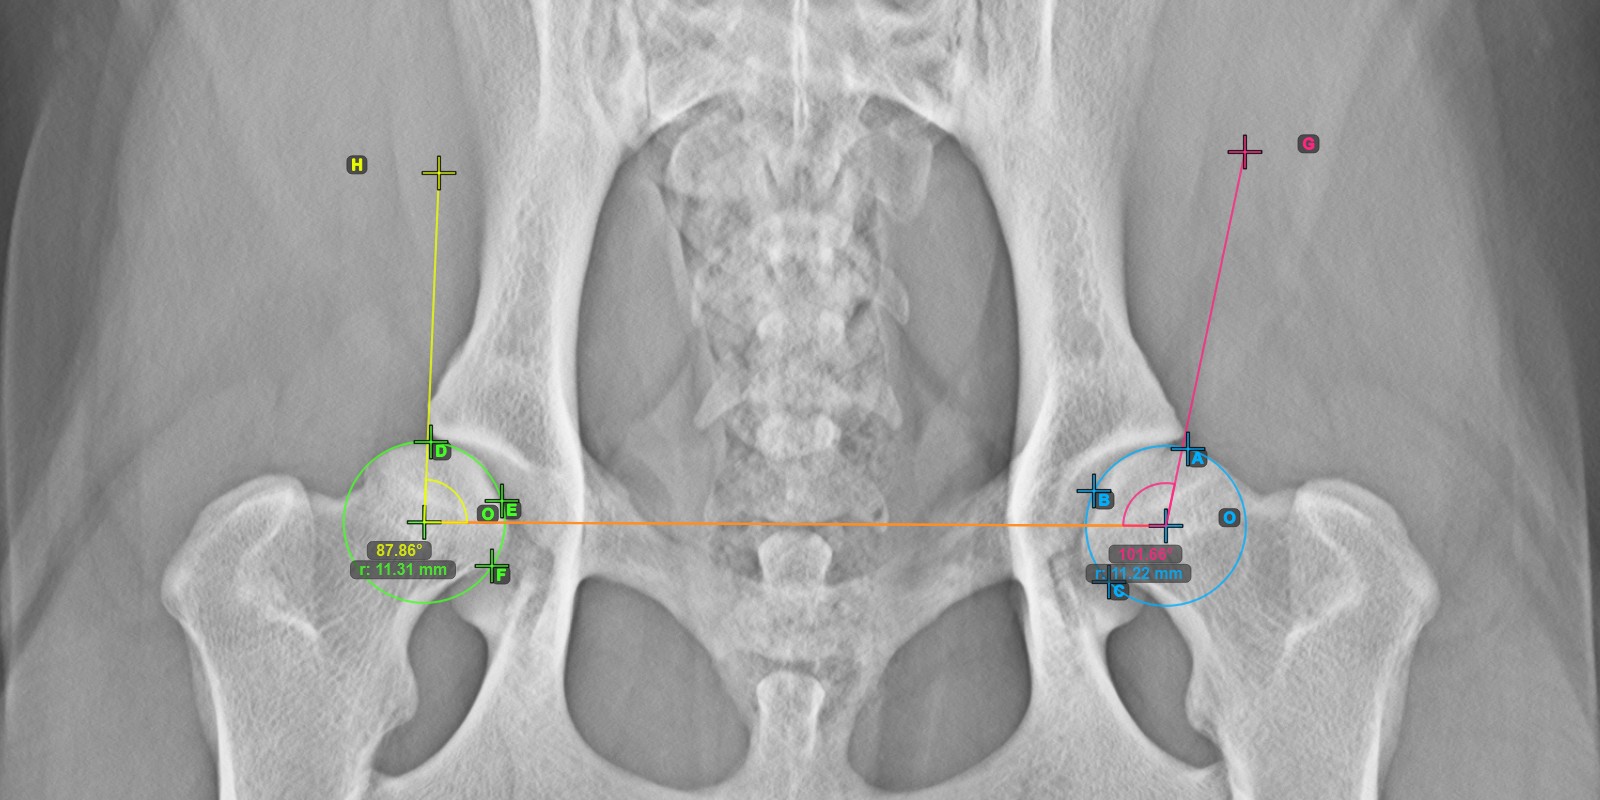

A lenti kép a vonal tipikus elhelyezkedését és a kiszámított Norberg szög mérését ábrázolja.

../../_images/image288.jpg